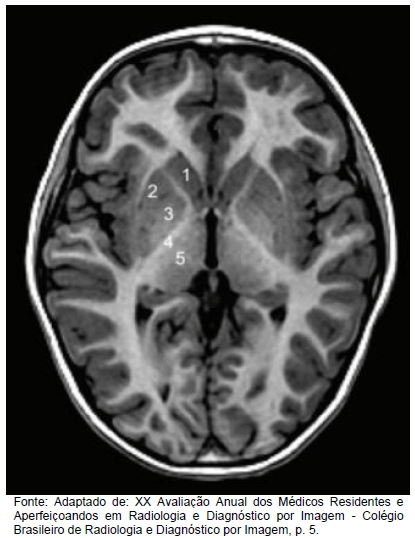

Analise a imagem abaixo.

Marque a opção em que as estruturas indicadas nessa imagem estão corretamente nomeadas.